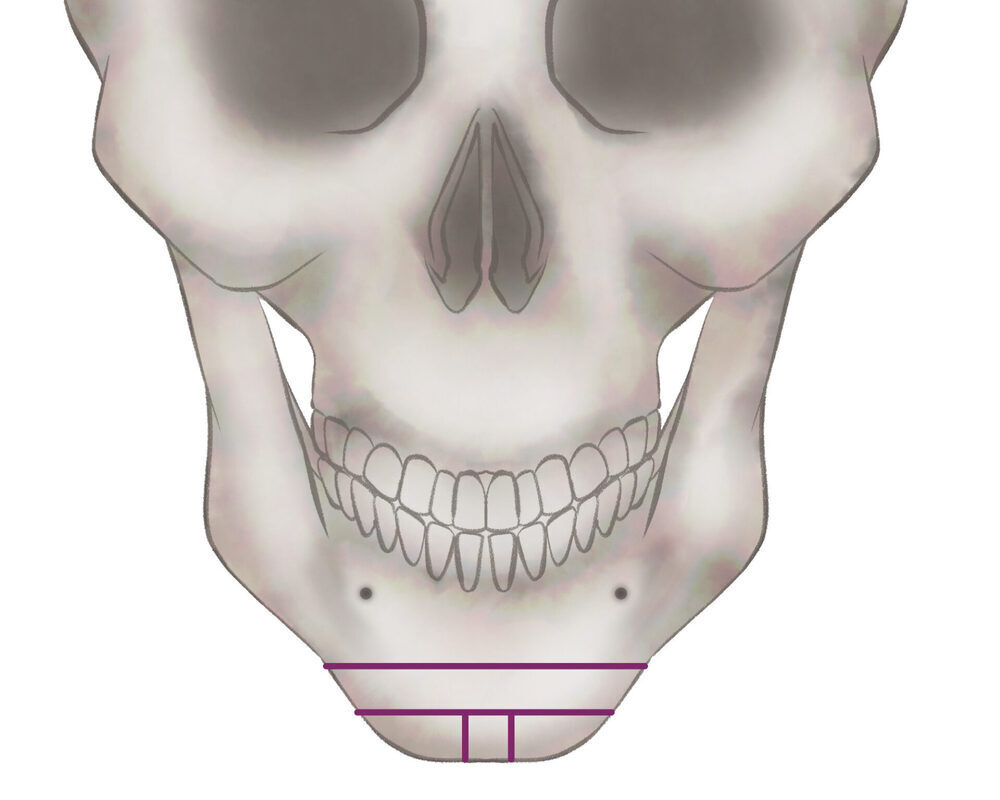

オトガイ骨切り(中抜き)

1.切開線をデザインします

2.骨を切除します

3.骨を移動させ段差を削ります

4.プレートで固定します